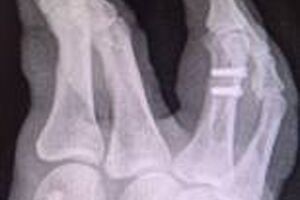

Es bestand am 22.05.2020 eine tragfähige Indikation für eine offene Reposition und osteosynthetische Versorgung der dislozierten Mehrfragmentfraktur am rechten Ringfingergrundglied. Das ärztliche Vorgehen war fehlerhaft, weil die Fraktur nicht achsengerecht versorgt wurde, ein Rotationsfehler verblieb und eine zeitnahe Korrektur nicht eingeleitet wurde. Die Ärzte der beklagten Klinik räumten in ihrer Stellungnahme ein, dass eine Fehlstellung des rechten Ringfingers vorgelegen habe. Die Drehfehlstellung des rechten Ringfingers sollte sich durch Krankengymnastik und Ergotherapie korrigieren. Eine zeitnahe Korrekturosteotomie war jedoch indiziert. Entscheidend zum Nachweis einer achsengerechten Stellung und zum Ausschluss eines verbliebenen Rotationsfehlers sind die klinischen intra- und postoperativen Stellungskontrollen der Finger beim aktiven und passiven Faustschluss und der Lauf der Finger (Abb.4)